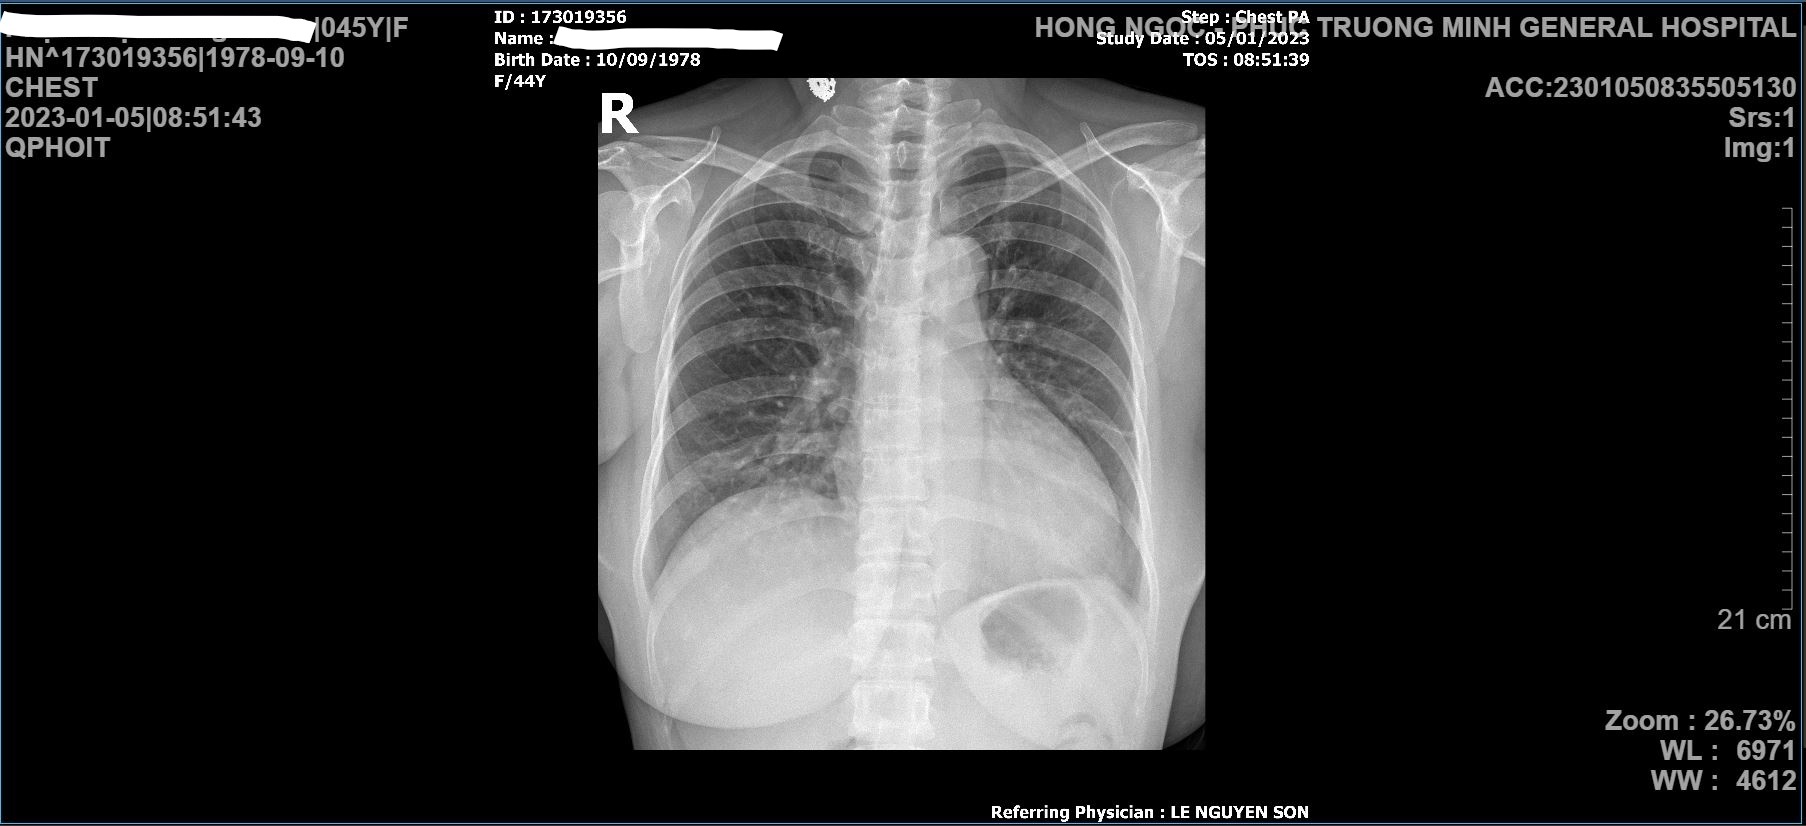

Chụp Xquang phổi Kết quả chụp Xquang phổi thời điểm nhập viện cho thấy bệnh nhân bị mờ toàn bộ phổi trái, đáy phổi phải

Nhằm xác định chính xác tình trạng bệnh, bệnh nhân H.G được chỉ định chụp Xquang tim phổi tại giường và thực hiện đo điện tim. Kết quả chụp Xquang cho thấy bệnh nhân bị mờ toàn bộ phổi trái, đáy phổi phải, chức năng hô hấp của phổi bị suy giảm nghiêm trọng.